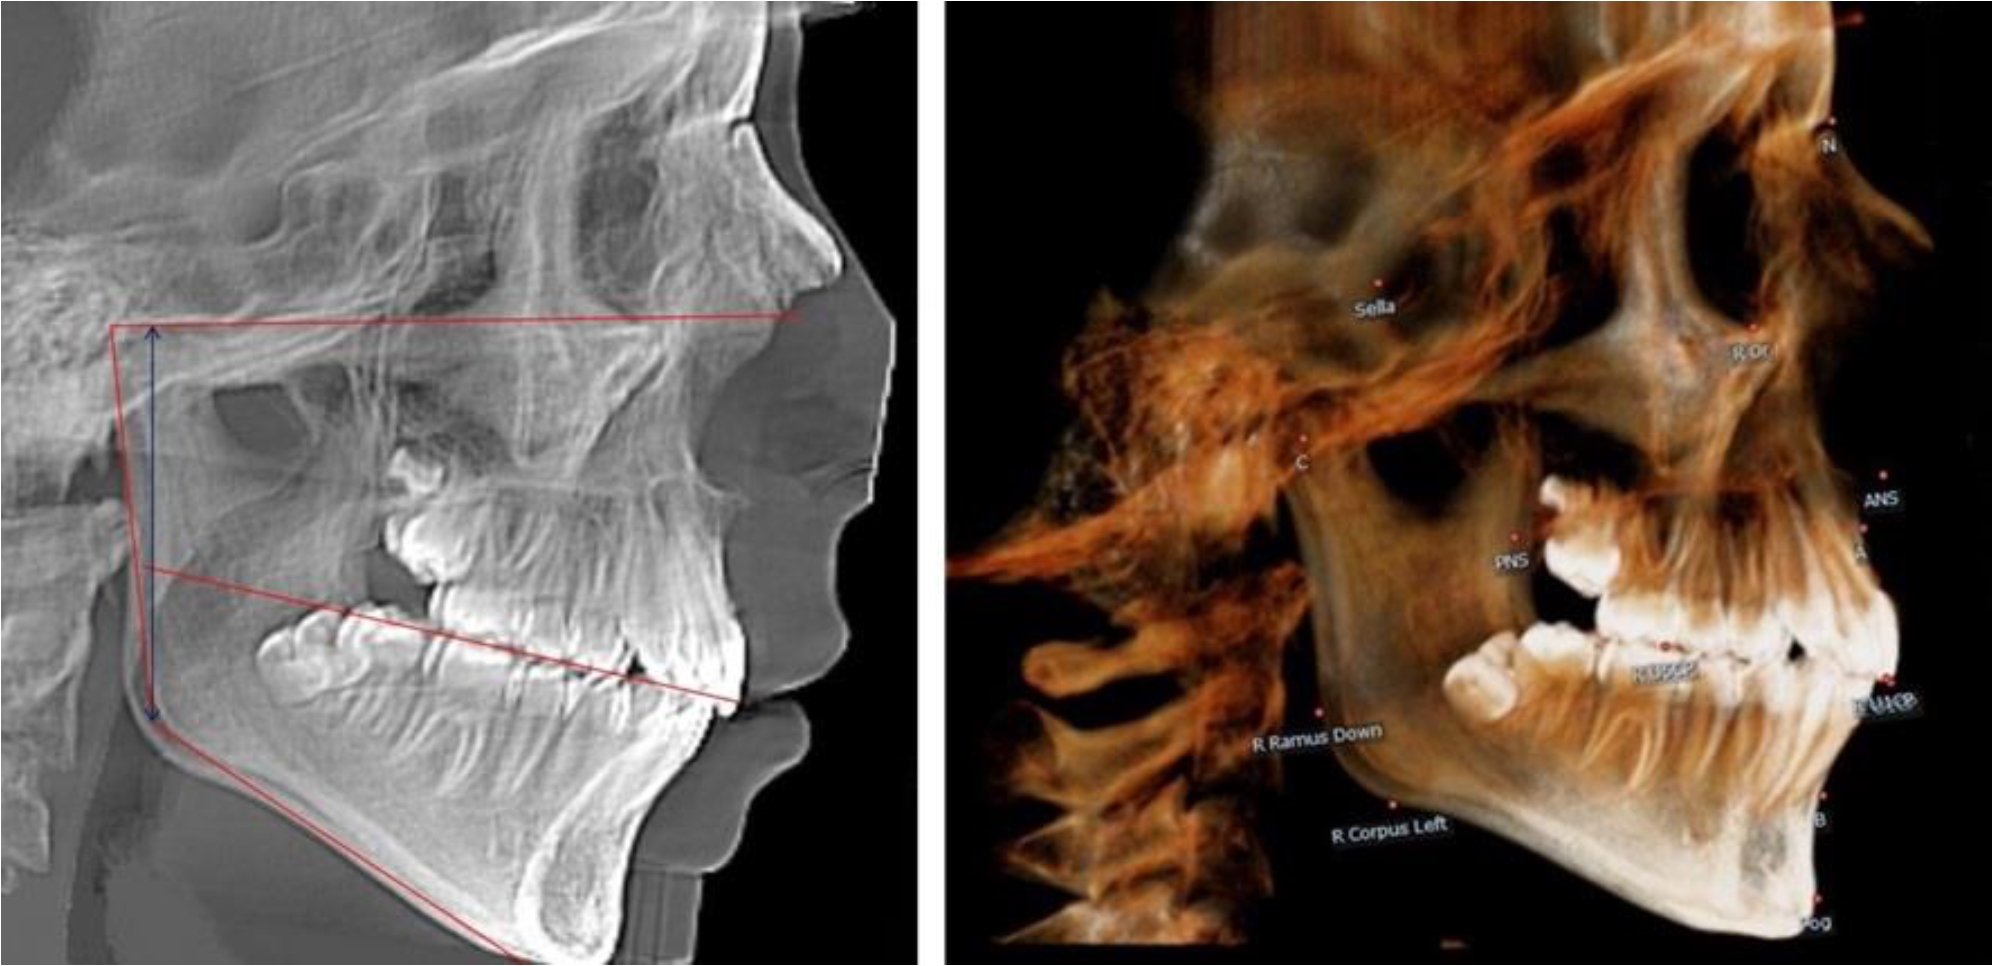

На всех парах рентгенограмм угол нижней челюсти, измеренный на телерентгенограмме, так же, как и в 1-й группе, соответствовал углу, полученному при построении угла на ортопантомограмме. Окклюзионная линия делила ветвь на два отдела (рис. 2).

Рис. 2. ТРГ и ОПТГ пациента после прорезывания первых постоянных моляров

Как на ортопантомограмме, так и на телерентгенограмме высота ветви у детей 2-й группы составляла (46,54 ± 2,87) мм, что было несколько больше, чем у детей 1-й группы (р ˂ 0,05). При этом высота верхней окклюзионно-суставной части была (25,42 ± 1,59) мм, а нижней – (21,12 ± 1,77) мм.

Таким образом, верхняя часть была несколько больше нижней, что и определяло рост обеих частей ветви.

Относительные показатели соразмерности частей ветви нижней челюсти показали, что отношение высоты верхней части ветви к нижней в среднем составляло 1,21 ± 0,12. Отношение общей высоты ветви к верхней ее части составляло 1,83 ± 0,13, а отношение общей высоты ветви к нижней ее части было 2,20 ± 0,16, и достоверных различий по относительному показателю отношения всей высоты к верхней и нижней челюсти нами не отмечено (р ˃ 0,05).

В 3-й группе были проанализированы 9 телерентгенограмм и 9 ортопантомограмм, что составило (8,49 ± 2,71) % от числа изученных рентгенограмм (рис. 3).

Рис. 3. ТРГ и ОПТГ пациента после смены молочных резцов

На всех рентгенограммах произошла смена молочных резцов постоянными. Окклюзионная линия делила ветвь на два отдела.

Высота ветви у детей у детей 3-й группы составляла (51,07 ± 2,72) мм, что было достоверно больше, чем у детей 1-й группы (р ˂ 0,05). При этом высота верхней окклюзионно-суставной части была (29,06 ± 1,44) мм, а нижней – (22,01 ± 1,59) мм. Высота верхней части была больше нижней, что и определяло особенности соразмерности частей ветви нижней челюсти в анализируемый возрастной период.

Относительные показатели соразмерности частей ветви нижней челюсти показали, что отношение высоты верхней части ветви к нижней в среднем составляло 1,32 ± 0,14. Отношение общей высоты ветви к верхней ее части составляло 1,75 ± 0,12, а отношение общей высоты ветви к нижней ее части было 2,32 ± 0,17, что и определяло особенности соразмерности частей ветви нижней челюсти в анализируемый возрастной период.